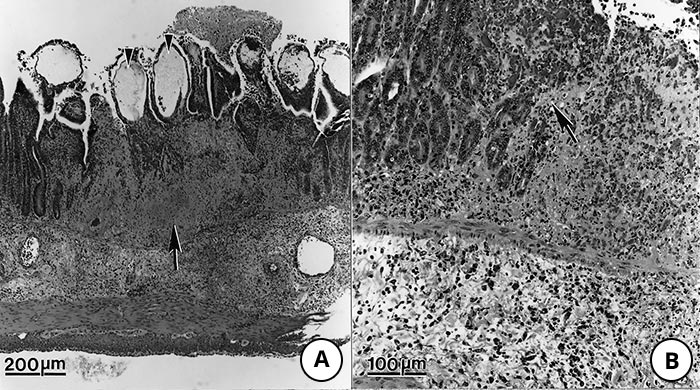

Figure 9 Lesions in the small intestine of pigs fed Toxoplasma gondii oocysts

- Note transmural necrosis (arrow) and ballooning of villi (arrowheads)

- Higher magnification of an area of inflammation and necrosis (arrow) adjacent to relatively unaffected epithelium

- High magnification of a villus showing oedema of lamina propria (arrowheads) and exudation into the lumen from an ulcer (arrow)

- Higher magnification of lamina propria showing tachyzoites (arrows). Haematoxylin and eosin stain